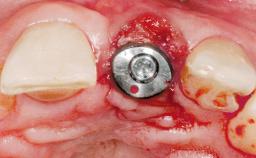

Immediate Placement of an Implant in a Maxillary Right Central Incisor Site

A 30-year-old female patient was referred to the office for the treatment of tooth 11. Her chief concern at the initial visit was to inquire, “Why is my tooth pink?” Upon clinical examination, it was determined that tooth 11 had a previous history of trauma and that the clinical crown had become noticeably pink in color as a result of internal resorption. This diagnosis was confirmed radiographically, indicating a large radiolucency involving the central and distal portions of the clinical crown. It was determined that restoration of this tooth was not possible, and that extraction was indicated. The presence of a mid-line diastema, which the patient wanted to reproduce, directed the treatment plan for tooth replacement utilizing a dental implant.